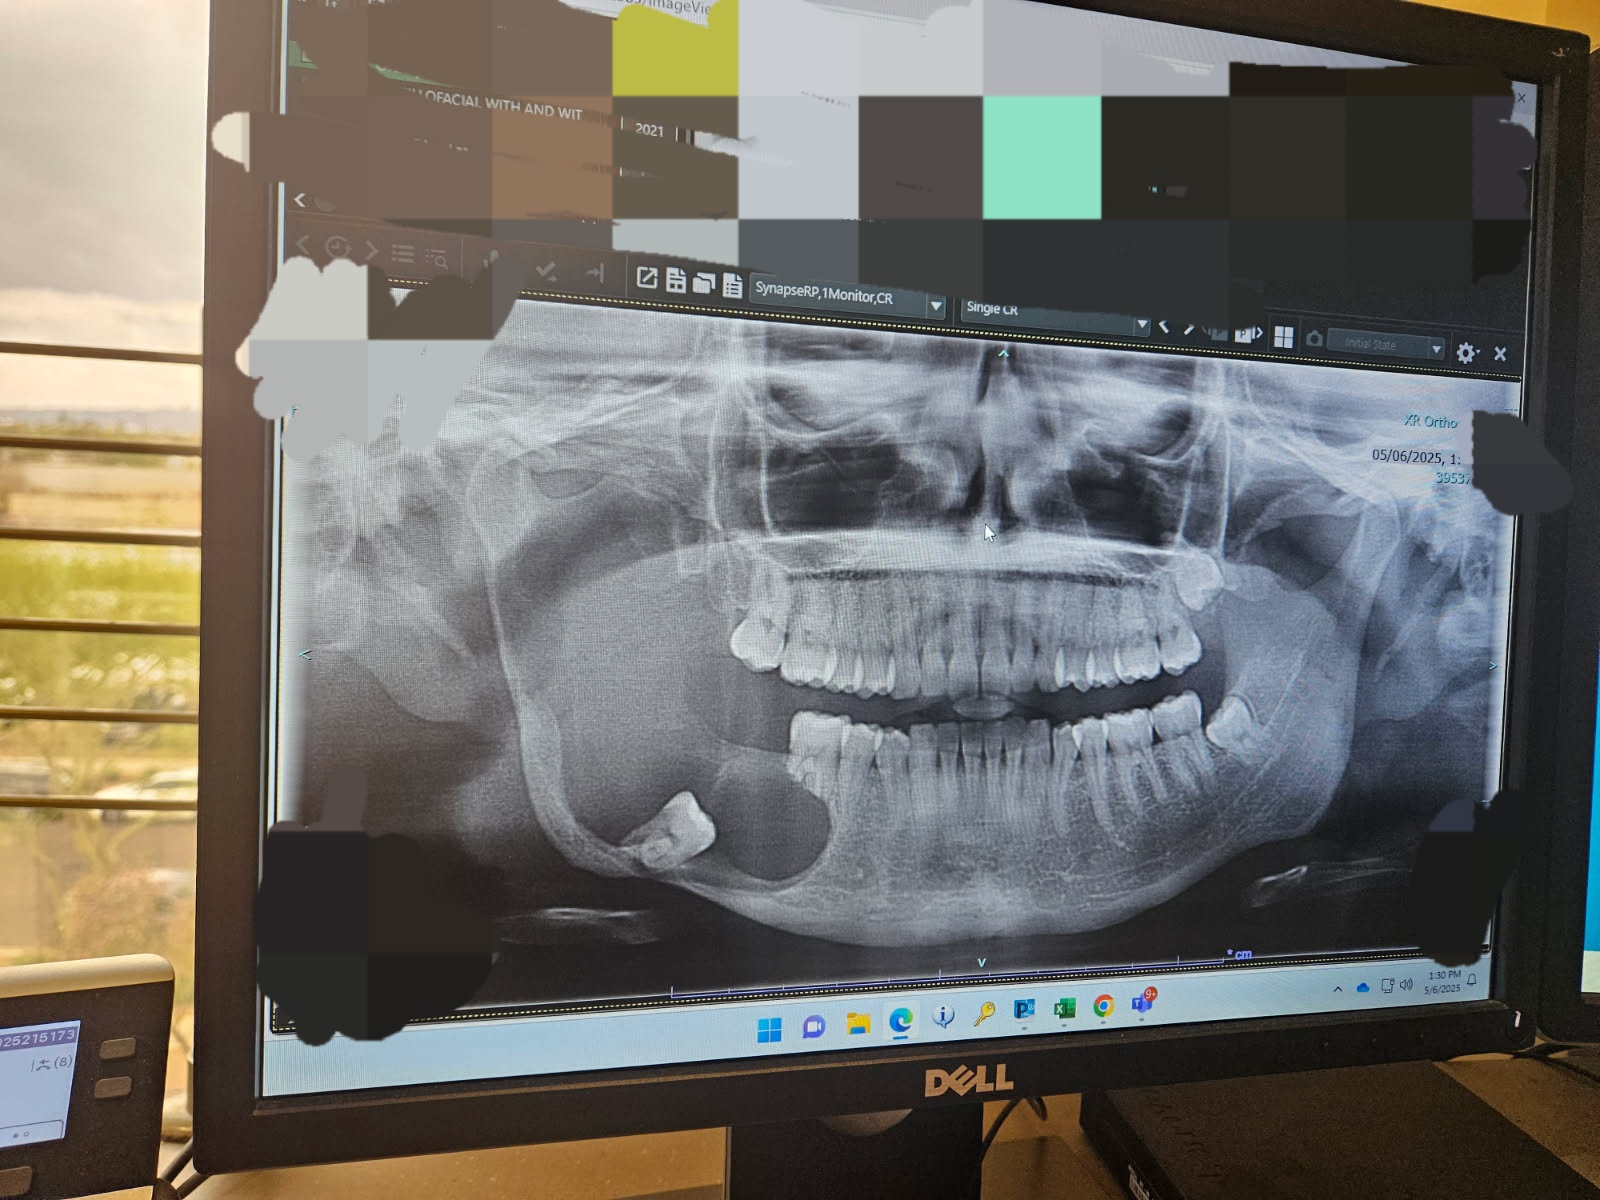

I am raising money for surgery expenses. I met with the surgeon yesterday to go over the latest scans on the tumor in my jaw. Now we're on a deadline to remove it before it reaches my skull base.

My jaw has eroded from the tumor/infection and they will need to remove bone from my leg to rebuild my jaw.